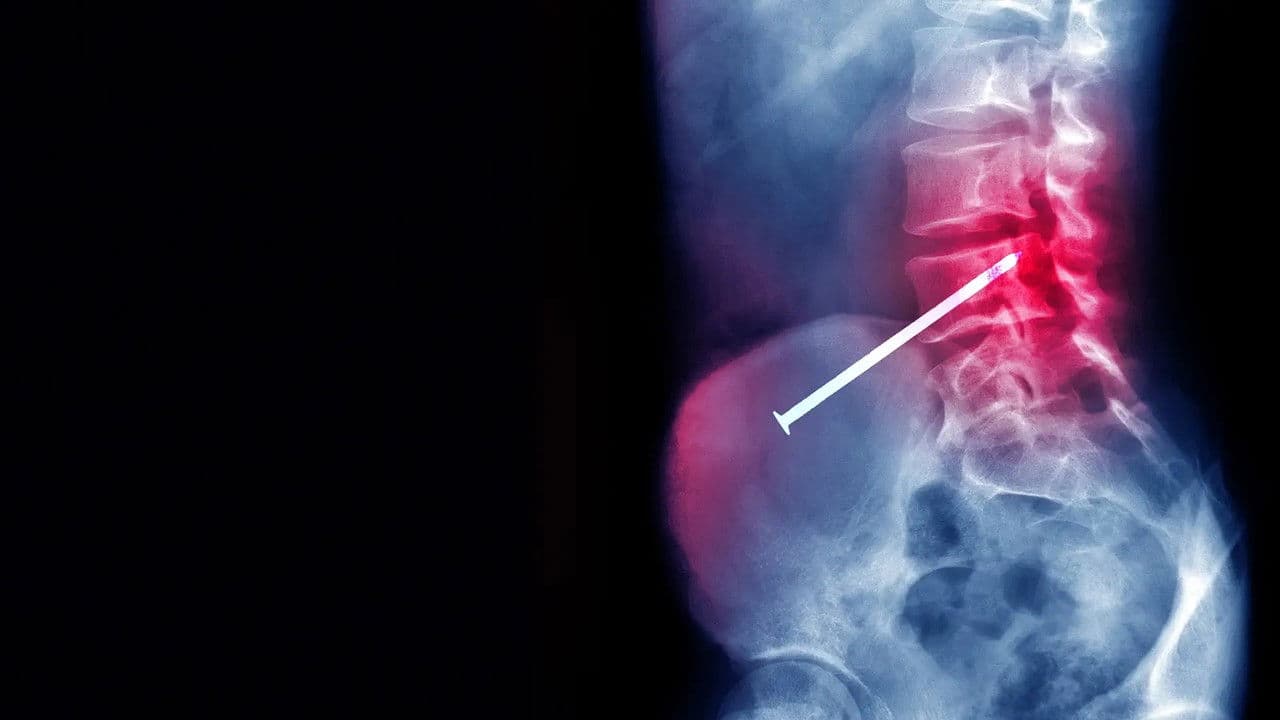

Des gens se retrouvent empalés sur des objets étonnants, et sont sauvés grâce aux compétences des médecins.